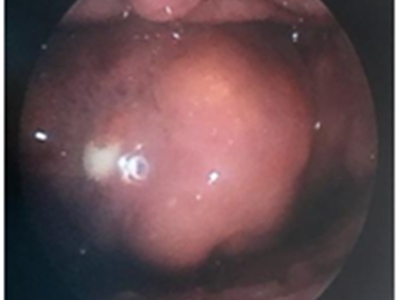

急性会厌炎起病急骤,有畏寒、发热、头痛等全身不适,多数患者体温在38-39℃。以剧烈的咽喉疼痛为主要症状,吞咽时加剧,重者饮水呛咳、流涎。喉镜下可见会厌舌面黏膜充血,高度肿胀水肿呈圆球状如卷曲香肠,肿胀可偏于一侧,偶见有黏膜溃疡。